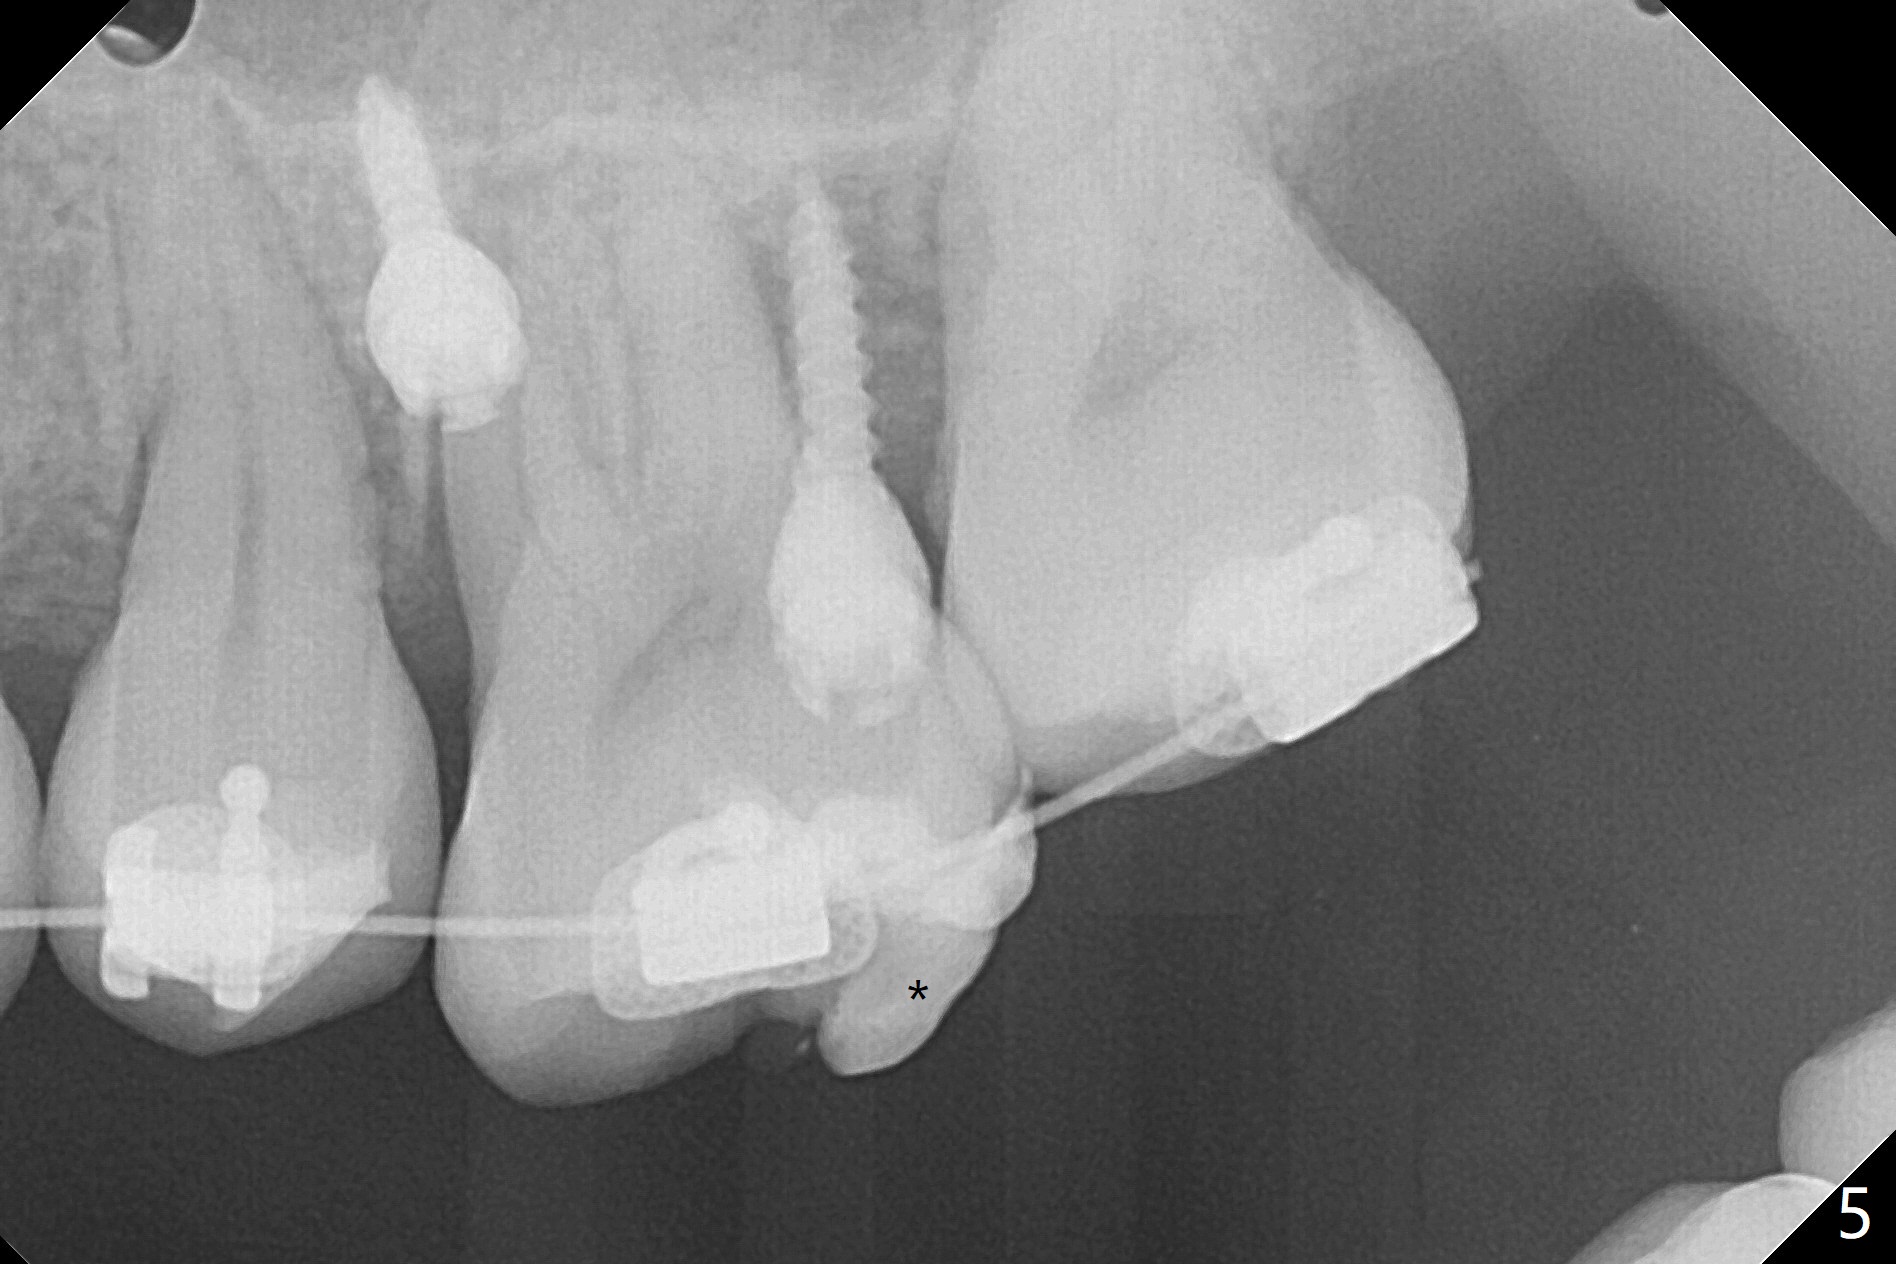

矫正器放置后一个月,正好有充裕时间,匆忙研究全景片(最好CT),好像左上6近中间隙大,近中颊侧,远中腭侧似乎是种植位点(图一:白圆圈),植入越高越宽,不容易伤及邻牙牙根。但是微型植体种植原则是必须种植在角化龈,减少炎症(以前不明白为什么)。当植体在移动牙龈植入时(图二:白箭头),牙龈浮起来,估计非角化牙龈也不能与植体产生紧密结合。取出后,完全可以在6近中颊侧角化龈植入,但是仔细检查发现远中颊侧角化龈更宽,所以在那里扎根(图二:黑箭头),因此腭侧就得选择近中(图三)。微型植体可以即刻使用,power chains常滑脱,压迫牙龈,在这个病例很可能进入远中牙间隙,所以需要在远中边缘嵴加树脂(图四,五:* (1.6x8mm))。第二天远中颊侧植体松动,取出后,插入2x10毫米一段式植体,仍然松动(图六)。CT显示植体下缘穿破牙槽骨(图七,骨质吸收严重与图八近中牙槽骨高度对比)。如果在近中颊侧重新植入微型植体,必须使用6毫米长植体(图九),所以最好在远中颊侧重新植入(图十:红色),缺损区(黑色)植骨。在使用14 niti时,左下7松动,病人同意拔除8,以后后推7,然后6种植(图十一:(左上8已拔除(x))),同时左上6远中植骨,左下8远中牙槽窝放置浸泡PRF液体胶原塞(图十二:1),近中牙槽窝粘性骨粉(2),最后牙槽窝上部PRF膜(3),PGA缝线。可能需要Cytoplast。